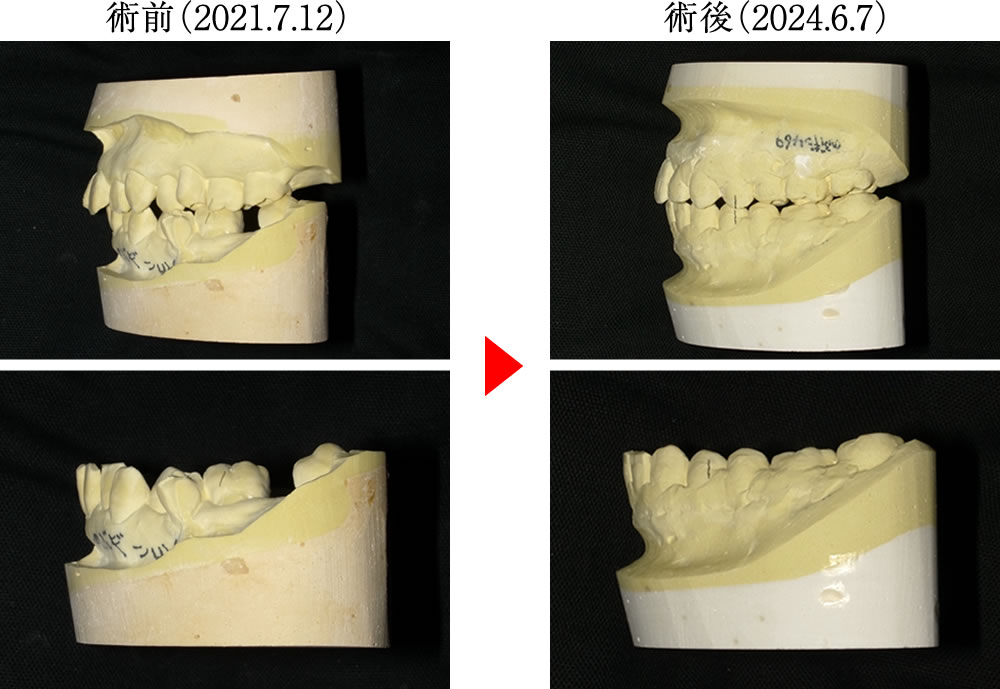

術前は歯列が狭く、歯並びも乱れていましたが、術後は歯列がダイナミックに拡大し、すべての歯が理想的に整列した美しいアーチとなりました。さらに親知らずも歯列に参加し、正しい位置に並んでいます。

左下の親知らずを有効に活用することで、咬合の再構成が可能となり、機能的な噛み合わせを実現しました。